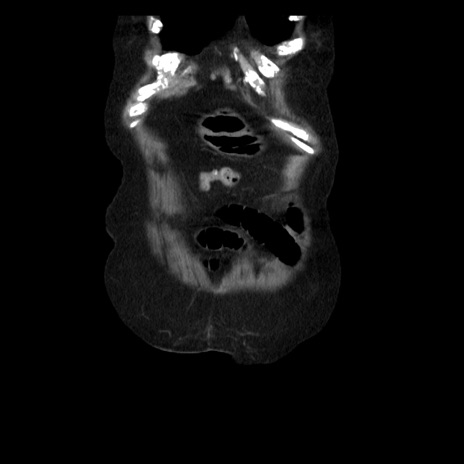

横断像